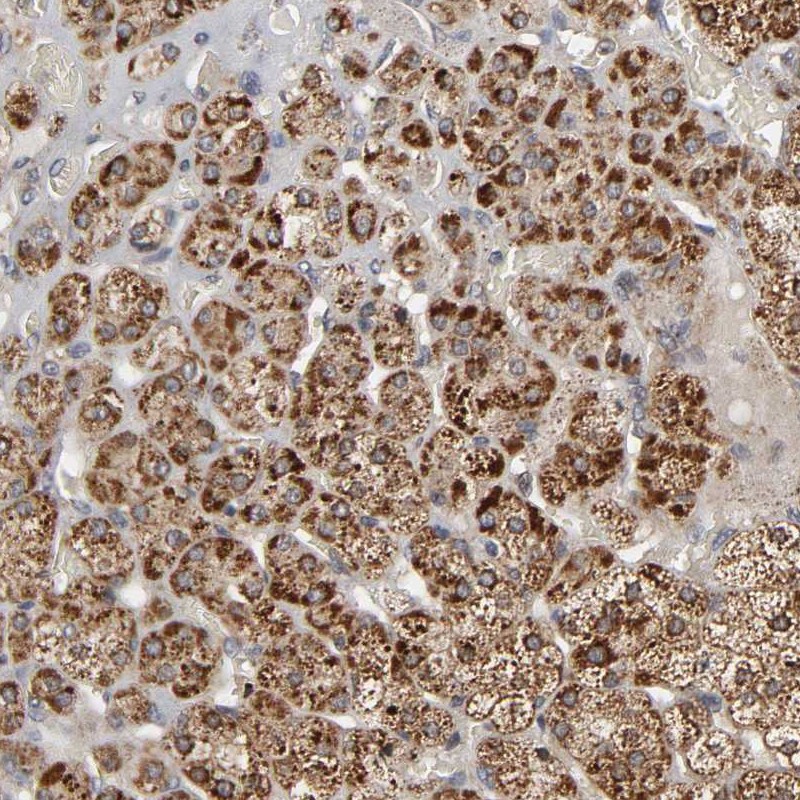

Immunohistochemical staining of human adrenal gland shows strong cytoplasmic positivity in cortical cells.